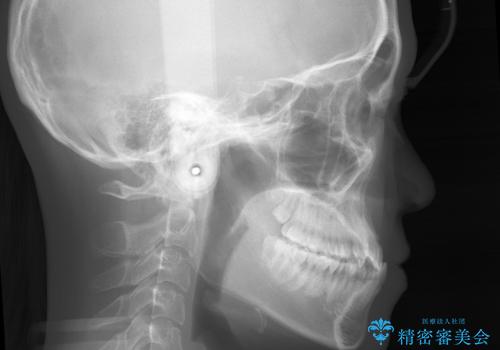

こちらの患者様の場合、上の前歯のガタつきが原因で口を閉じる際に上下の前歯の先端同士が先に当たってしまい、そこからさらに深く噛み込もうとすると下顎が前にずれていってしまうという、機能性の反対咬合であることが検査の結果わかりました。

その原因は ①骨格的問題 ②機能的問題 の2つに大きく分かれます。

①に関しては外科的手術を併用した矯正治療を必要とする場合が多く、大学病院や専門の設備を備えた医院での治療が必要となります。

原因が②であった場合は、手術を必要とせず口腔内ではの位置を変えてあげるだけで噛み合わせや顔貌を変化させることができる場合があります。